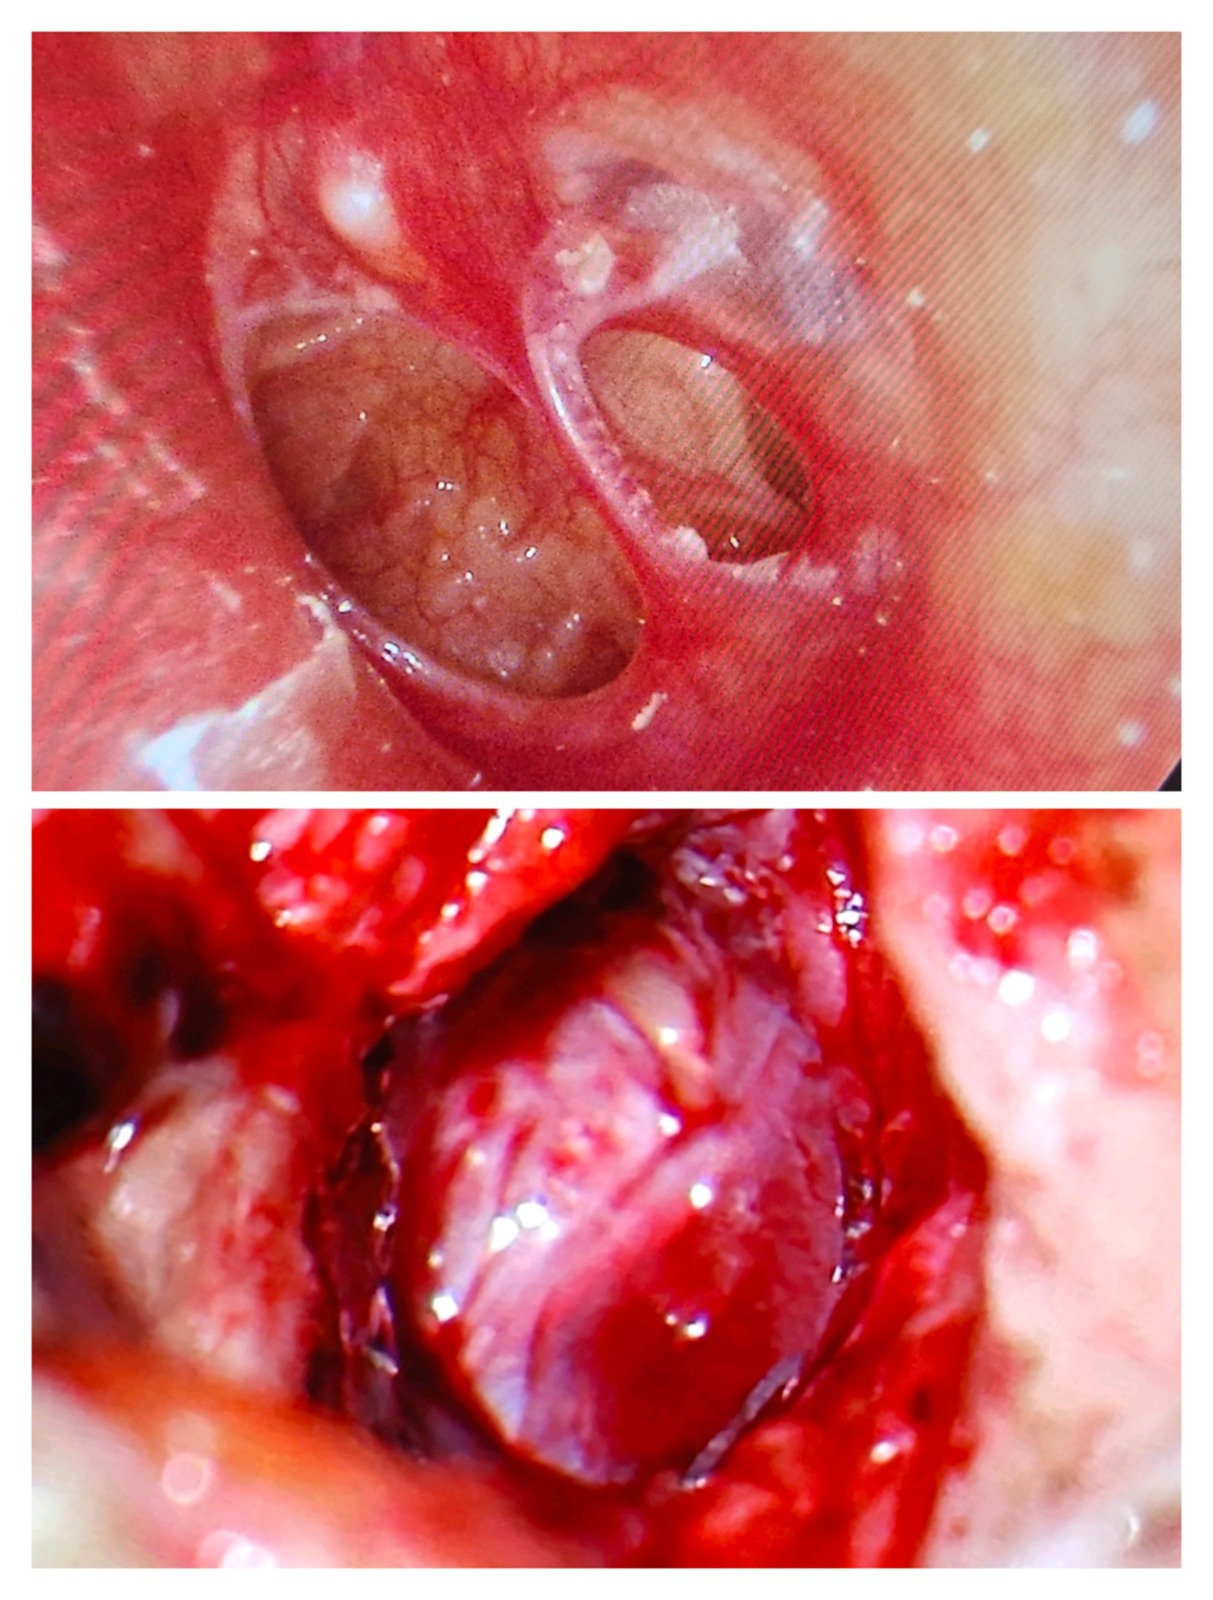

1. Tympanoplasty (Eardrum Repair Surgery)

Tympanoplasty repairs a perforated or damaged eardrum using advanced microscopic techniques.

2. Stapedotomy (Otosclerosis Hearing Surgery)

Stapedotomy is performed when the stapes bone becomes fixed due to otosclerosis, causing hearing loss.

Dr. Muddazir replaces the fixed stapes bone with a prosthetic, restoring natural sound conduction.

3. Ossiculoplasty (Middle Ear Bone Reconstruction)

Ossiculoplasty reconstructs or replaces damaged ossicles (hearing bones: malleus, incus, stapes).